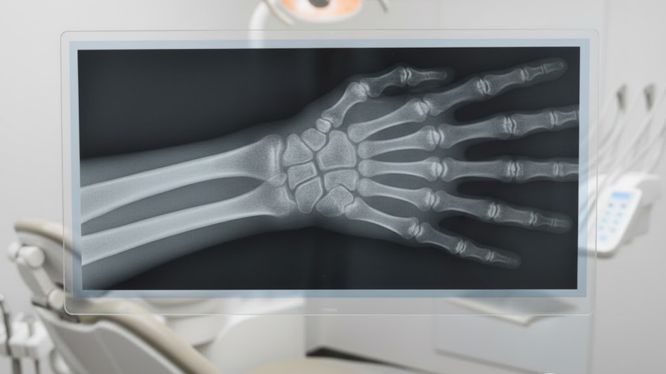

🔹 Radiografía carpal

Indicada principalmente en niños y adolescentes 👧🧒

Además, sirve para:

• Comparar crecimiento óseo con edad cronológica

• Determinar el mejor momento para iniciar ortodoncia u ortopedia

📌 Es clave para tratamientos bien planeados y a tiempo.